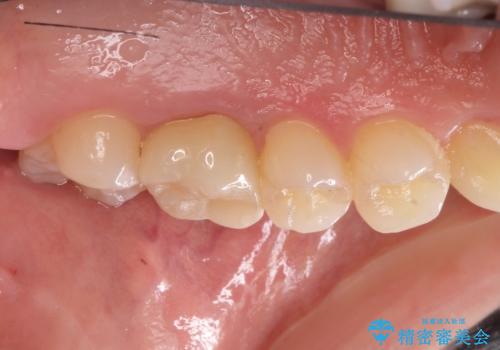

金属の奥歯 → 白い奥歯 根管治療からのやり直し

- 再根管治療→土台の築造 を行った上でのかぶせ物のやり替えをおこないました。

神経の無い歯のかぶせ物をやり替える際は、是非根管治療からしっかりやり直すことをおすすめします。

かぶせ物の種類:Bellezza